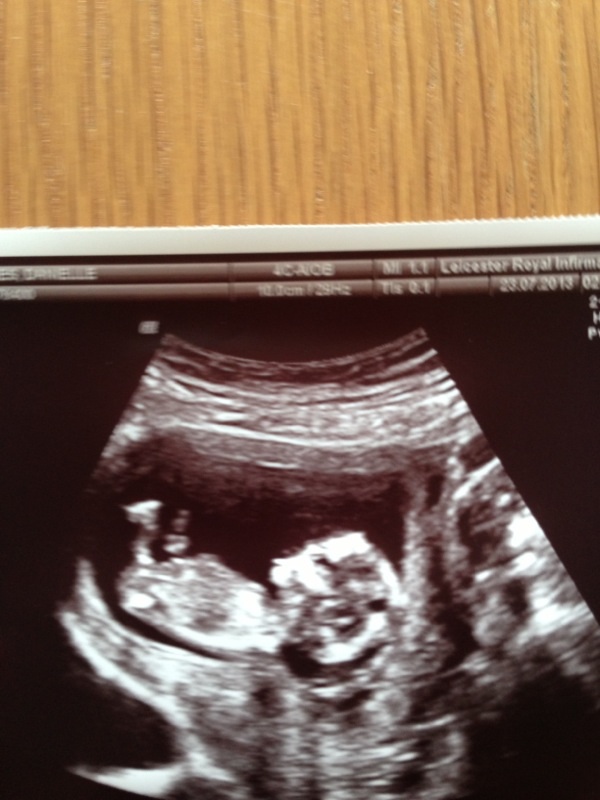

Hi this is my third child looking at just the skull theory can anybody tell me boy or girl? I had mixed guesses on the nub theory so thought I would try the skull theory can't wait to find out :) any guesses are much appreciated :)Attachment 13218